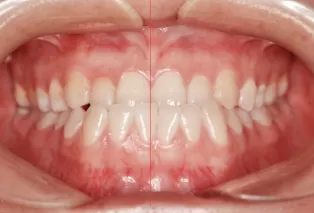

Intraoral photos